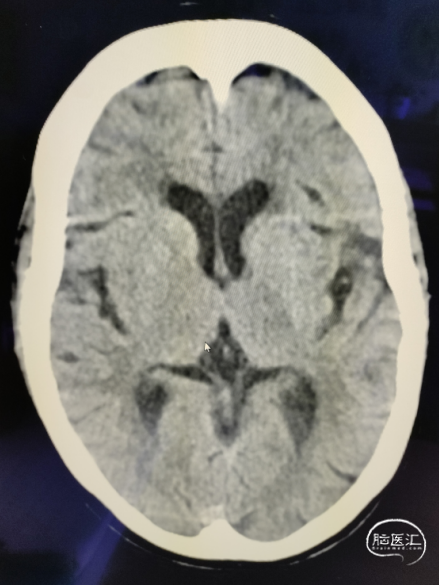

颅脑NCCT见右侧大脑总动脉高密度征,ASPECTS评分10分。

术前